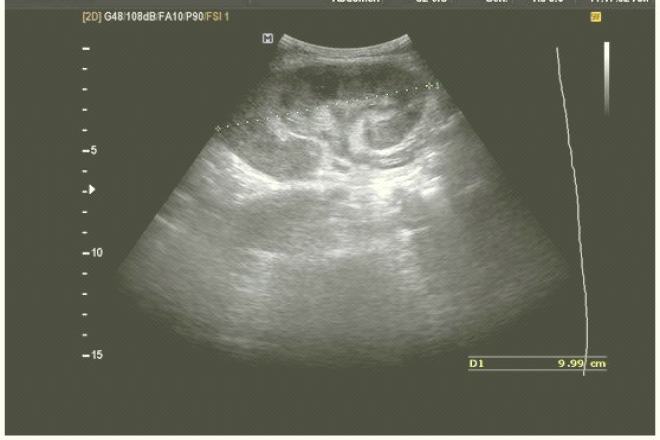

Síndrome de ovario poliquístico

Síndrome de ovario poliquístico Los criterios iniciales para el diagnóstico de síndrome de ovario poliquístico fueron (en orden de importancia): 1) hiperandrogenismo o hiperandrogenemia, 2) oligoovulación, 3) exclusión de otros trastornos conocidos, y quizá, 4) ovarios poliquísticos al ultrasonido (controversial). Años más tarde se modificaron a: 1) oligoovulación o anovulación,